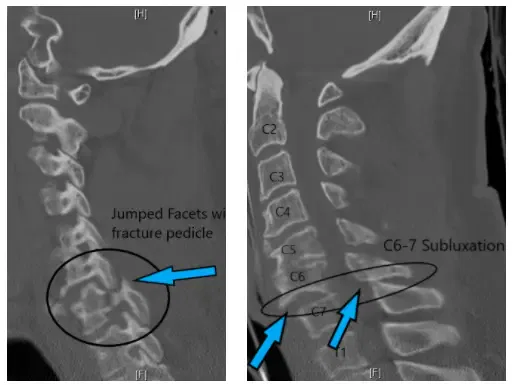

Se realizó una tomografía computarizada urgente que mostró lesión de la columna cervical con luxación unilateral facetaria de C6-7 en el lado derecho con fractura del pedículo junto con sublixación de C6 sobre la vértebra C7.

La luxación facetaria causaba compresión de la médula espinal a nivel del cuello y el paciente tenía un déficit neurológico incompleto. Necesitó una cirugía urgente para eliminar la compresión de la médula espinal.